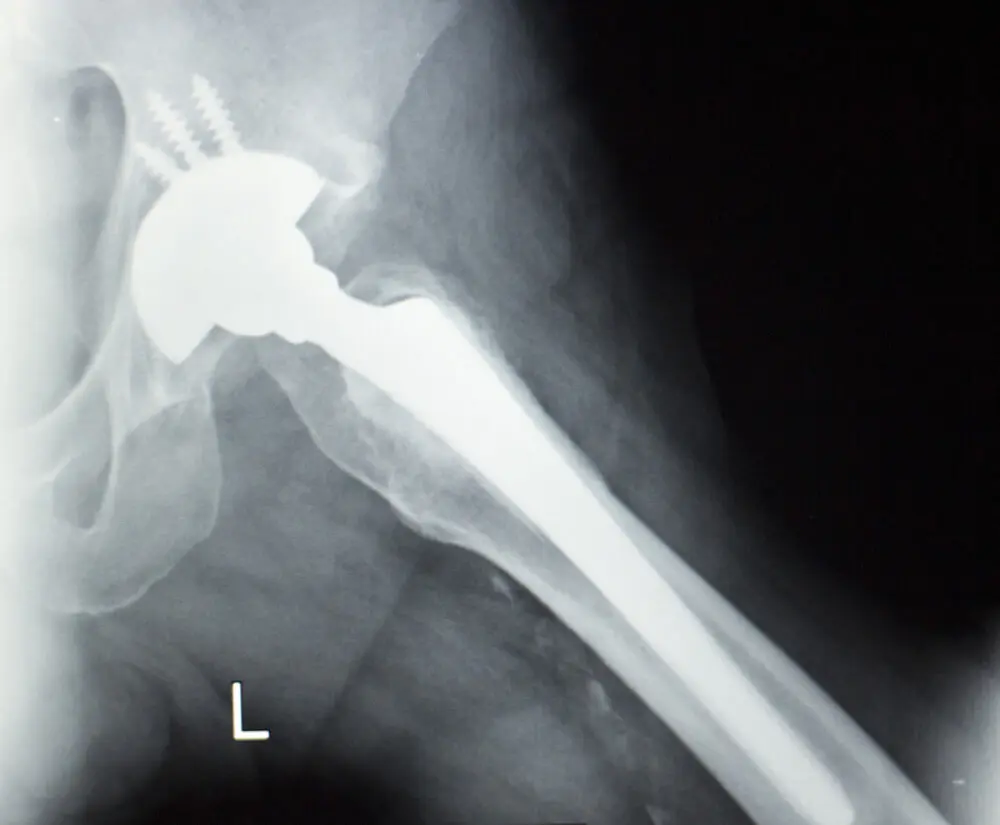

Stryker Accolade and LFit Hip Lawsuit Filed Over Elevated Metal Ions in Blood, Resulting in Revision Surgery November 29, 2017 Irvin Jackson Add Your Comments Metal debris shed from Stryker Accolade and LFit hip implant components caused a Maine man to develop elevated metal ions in his blood, which resulted in failure of the hip replacement and the need for revision surgery, according to a recently-filed lawsuit. Mark Irving and his wife, Lorraine, filed a complaint (PDF) against Howmedica Osteonics Corporation, doing business as Stryker Orthopedics, on November 9 in the U.S. District Court for the District of Maine. According to the lawsuit, Irving underwent left total hip replacement in December 2011, during which he received a Stryker LFit Anatomic V40 CoCr Femoral Head, with a Stryker Accolade TMZF Plus Hip Stem, among other components. However, by October 2016, he had to undergo revision surgery to have the devices removed due to failure of the hip implant, which was allegedly caused crevice corrosion where the two components met. Stay Up-to-Date About hip replacement lawsuits AboutLawsuits.com sends a weekly digest email with information about recalls, lawsuits and warnings that may impact your family, which will include any new hip replacement lawsuit updates or developments. "*" indicates required fields Email* SIGN ME UP Δ Learn More Stay Up-to-Date About Hip Replacement Lawsuits AboutLawsuits.com sends a weekly digest email with information about recalls, lawsuits and warnings that may impact your family, which will include any new hip replacement lawsuit updates or developments. "*" indicates required fields Email* SIGN ME UP Δ Learn More “After implantation, Plaintiff Mark Irving developed pain in his replaced left hip,” the lawsuit states. “Metal ion testing demonstrated elevated cobalt and chromium levels.” After receiving similar reports involving hip failures, a Stryker LFit v40 hip recall was issued by the manufacturer in August 2016, impacting certain large-diameter femoral heads. At that time, Stryker acknowledged that a higher-then-expected number of individuals were experiencing problems with trunnion failure, metal wear, adverse tissue reactions and other complications. The case filed by Irving joins a growing number of other hip replacement lawsuits filed in recent months by individuals have suffered complications that resulted in revision surgery only a few years after receiving the implant. In particular, complications with the Stryker Accolade stem in combination with the LFit V40 femoral head have resulted in reports of excessive metallic debris, limited range of motion, disassociation, fractures and failed hip replacements. Given similar questions of fact and law raised in complaints filed throughout the federal court system, the U.S. Judicial Panel on Multidistrict Litigation (JPML) established coordinated pretrial proceedings earlier this year for all lawsuits involving use of the Stryker LFit v40 head, centralizing the cases before U.S. District Judge Indira Talwani in the District of Massachusetts. Similar centralized proceedings were previously established in the federal court system following a 2012 Stryker Rejuvenate and ABG II recall, which resulted in thousands of lawsuits brought by individuals nationwide. Following coordinated discovery in that litigation, the manufacturer agreed to pay more than $1 billion in hip implant settlements to resolve cases for individuals who required revision surgery after these recalled implant failed. Written by: Irvin Jackson Senior Legal Journalist & Contributing Editor Irvin Jackson is a senior investigative reporter at AboutLawsuits.com with more than 30 years of experience covering mass tort litigation, environmental policy, and consumer safety. He previously served as Associate Editor at Inside the EPA and contributes original reporting on product liability lawsuits, regulatory failures, and nationwide litigation trends. Tags: Hip Replacement System, Howmedica, Metal Blood Poisoning, Stryker, Stryker Accolade, Stryker LFit More Hip Replacements Lawsuit Stories Biomet Hip Lawsuit Filed Over Defective M2A Metal-on-Metal Implant December 26, 2024 Zimmer Biomet Lawsuit Filed Over RibFix Blu Implant Fracture September 25, 2024 Zimmer Biomet CPT Hip System Linked to Increased Risk of Thigh Bone Fractures, FDA Warns September 18, 2024 0 Comments URLThis field is for validation purposes and should be left unchanged.Share Your CommentsFirst Name*Last NameEmail* Shared Comments*This field is hidden when viewing the formI authorize the above comments be posted on this page Yes No Post Comment I authorize the above comments be posted on this page Weekly Digest Opt-In Yes, send me a weekly email with the latest lawsuits, recalls and warnings. Want your comments reviewed by a lawyer?To have an attorney review your comments and contact you about a potential case, provide your contact information below. This will not be published.Contact Phone #Alt Phone #Private CommentsNOTE: Providing information for review by an attorney does not form an attorney-client relationship.CAPTCHAGA SourceGA CampaignGA MediumGA ContentGA Term Δ MORE TOP STORIES Ovarian Cancer Lawsuit Over J&J Talcum Powder Asbestos Risks Goes Before California Jury (Posted: today) The first of three California state court talcum powder lawsuits began last week in Los Angeles, involving two women diagnosed with ovarian cancer. MORE ABOUT: TALCUM POWDER CANCER LAWSUITSTalc Powder Cancer Verdicts and Lawsuits Continue To Pile Up Against Johnson & Johnson (10/30/2025)J&J Faces Talcum Powder Lawsuit in UK Brought By More Than 3,000 Plaintiffs (10/17/2025)Lawyers in Talcum Powder Bellwether Lawsuit To Meet for Final Pretrial Conference Nov. 5 (10/10/2025) Lawsuits Over Ozempic Vision Loss and Gastrointestinal Injuries Will Be Separately Managed in NJ State Court (Posted: yesterday) Lawsuits over Ozempic and Wegovy vision loss will be consolidated for pretrial proceedings in New Jersey, separate from claims involving gastrointestinal injuries. MORE ABOUT: OZEMPIC LAWSUITJudge Extends Deadlines To Address GLP-1 Lawsuit ‘Cross-Cutting’ Issues (10/28/2025)Ozempic Gastroparesis Problems Persisted After Injections Stopped, Lawsuit Alleges (10/21/2025)Ozempic, Wegovy Kidney Side Effects Highlighted in New Study (10/10/2025) GalaFLEX Breast Mesh Problems Were Highlighted in Warnings Issued by Former Becton Dickinson Medical Director (Posted: 4 days ago) Former Becton Dickinson safety officer Dr. Hooman Noorchashm warns that the company’s GalaFLEX mesh is being used off-label in breast reconstruction without FDA approval, as lawsuits investigate whether the manufacturer failed to warn about its potential risks. MORE ABOUT: BREAST MESH LAWSUITBreast Mesh Reconstruction Surgery Gaining Popularity Despite Safety Concerns, Lawsuits (11/10/2025)Internal Bra Mesh Failure Stories Highlight Risk of Pain, Infections and Other Problems (11/06/2025)Internal Bra Side Effects Raise Questions About Manufacturers’ Knowledge of Mesh Failures (10/27/2025)